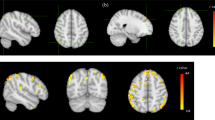

Negative symptom factor DE is associated with perfusion in the supplementary motor area and the anterior cerebellum

We observed an association between severity of DE and rCBF bilaterally in the pre-supplementary and supplementary motor area (SMA) as well as the anterior lobe of the cerebellum and the cerebellar vermis (Fig. 1). Specifically, severe reduced emotional and speech expression (DE) was associated with higher perfusion in these regions. Conversely, we observed no significant association between brain perfusion and the second main negative symptom factor (MAP). In addition, comparing patients and controls independent of NS identified lower rCBF in patients within the right planum temporale (see Table S2).

Correlations between resting-state perfusion and negative symptom severity according to the Clinical Assessment Interview for Negative Symptoms (CAINS). Depicted clusters are significant at p(FWE-corr) < 0.05 at peak or cluster level. IFG Inferior frontal gyrus, MFG Middle frontal gyrus, SMA Supplementary motor area, PMd Dorsal premotor area, PMv Ventral premotor area, ACC Anterior cingulate cortex, LiG Lingual gyrus, NAcc Nucleus accumbens, STG Superior temporal gyrus, PoG Postcentral gyrus, SMG Supramarginal gyrus.

For all imaging analyses, we included age, six motion parameters, olanzapine equivalents, PANSS positive subscore, duration of illness, years of education and diazepam equivalents as covariates of no-interest. In addition, voxels with <10 [ml/100 g/min] blood flow were excluded from all analyses to exclude voxels in white matter118. We applied a statistical threshold of p < 0.05 family wise error corrected for multiple testing (FWE-corr). We present results for the Clinical Assessment Interview for Negative Symptoms (CAINS) corrected at peak- or cluster level in the main manuscript. Additionally, results for the Scale for the Assessment of Negative Symptoms (SANS) corrected for multiple testing (FWE-corr) at peak- or cluster level are presented in the supplementary material (Table S1). We produced figures using SPM12 and the SPM xjView toolbox (https://www.alivelearn.net/xjview). For illustration purposes, we produced images at p < 0.001 uncorrected with a minimum cluster size of 350 voxels. The minimum cluster size of 350 voxels was chosen to guarantee that only brain regions surviving the strict FWE corrections <0.05 are displayed. We extracted the mean perfusion values post-hoc from significant clusters for all patients and healthy controls using MarsBaR124 and plotted extracted brain perfusion values and NS severity.